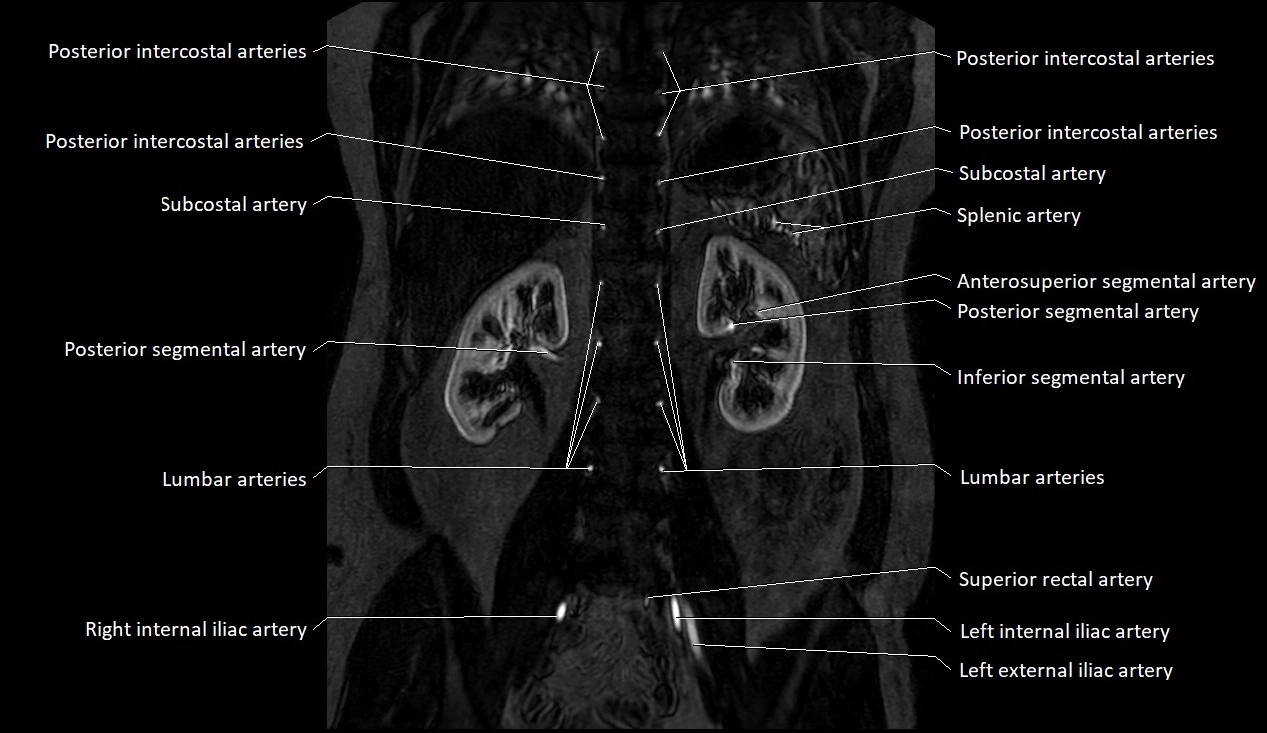

MRI images

image